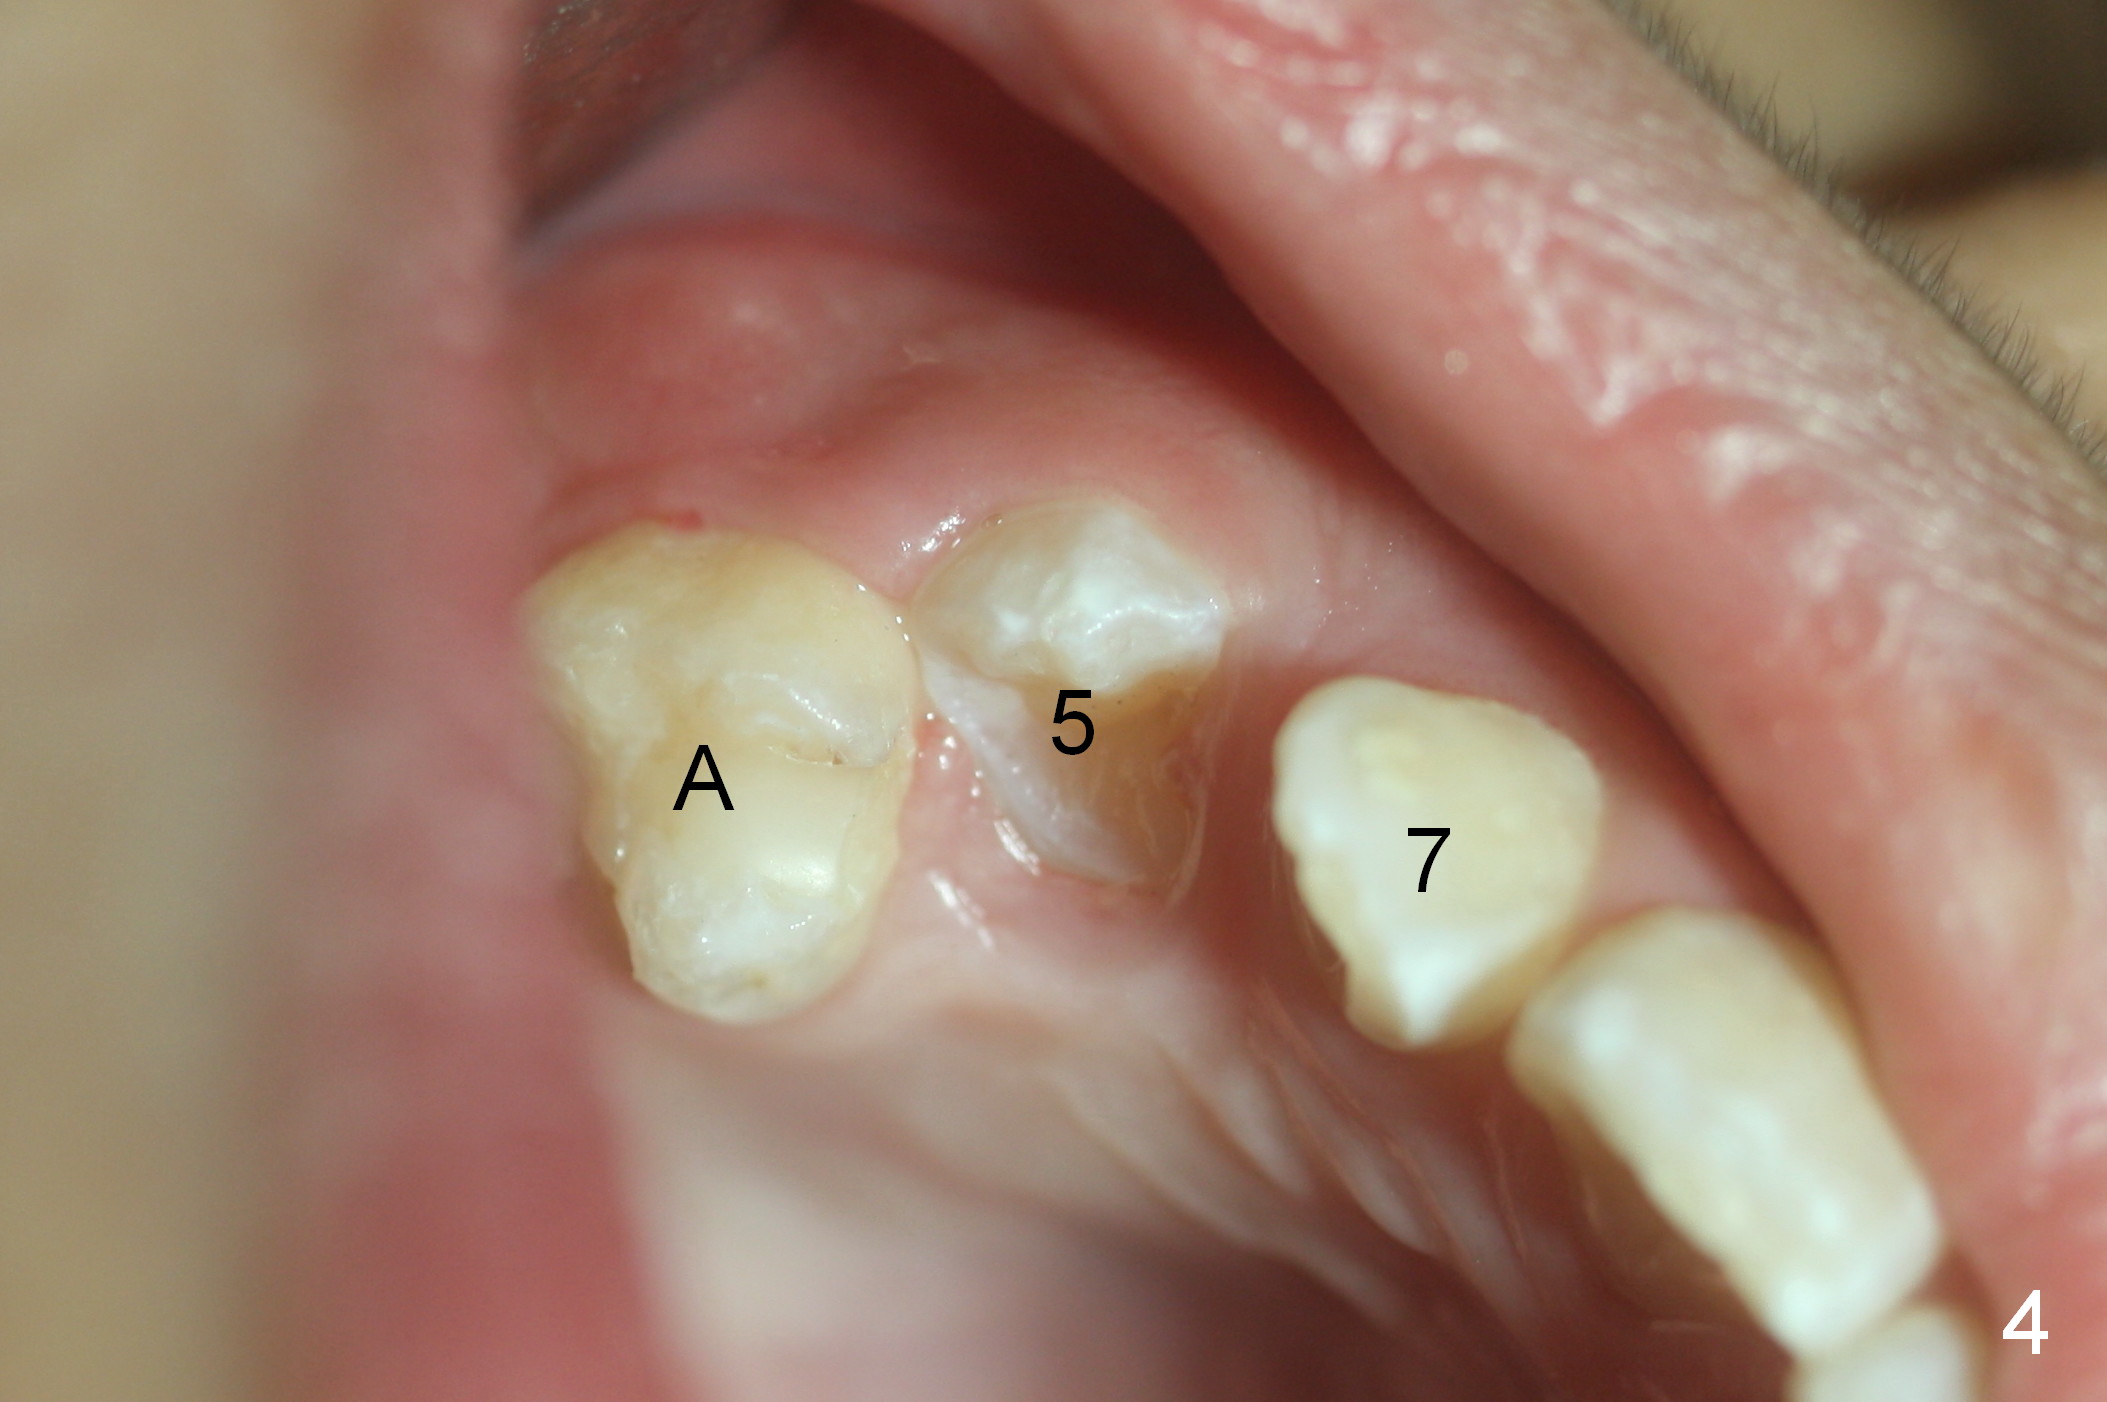

For upper and lower right crowding, series extraction is planned. First the tooth B is extracted. Within 1.5 months, the tooth #5 is erupting (Fig.4 (9 years 4 months old)). It will be extracted once it is fully erupted.

One month later, the tooth #5 erupts more (Fig.5,6) and is extracted (Fig.8-10). The tooth S is to be extracted to make room for #27 and 28 eruption (Fig.7).